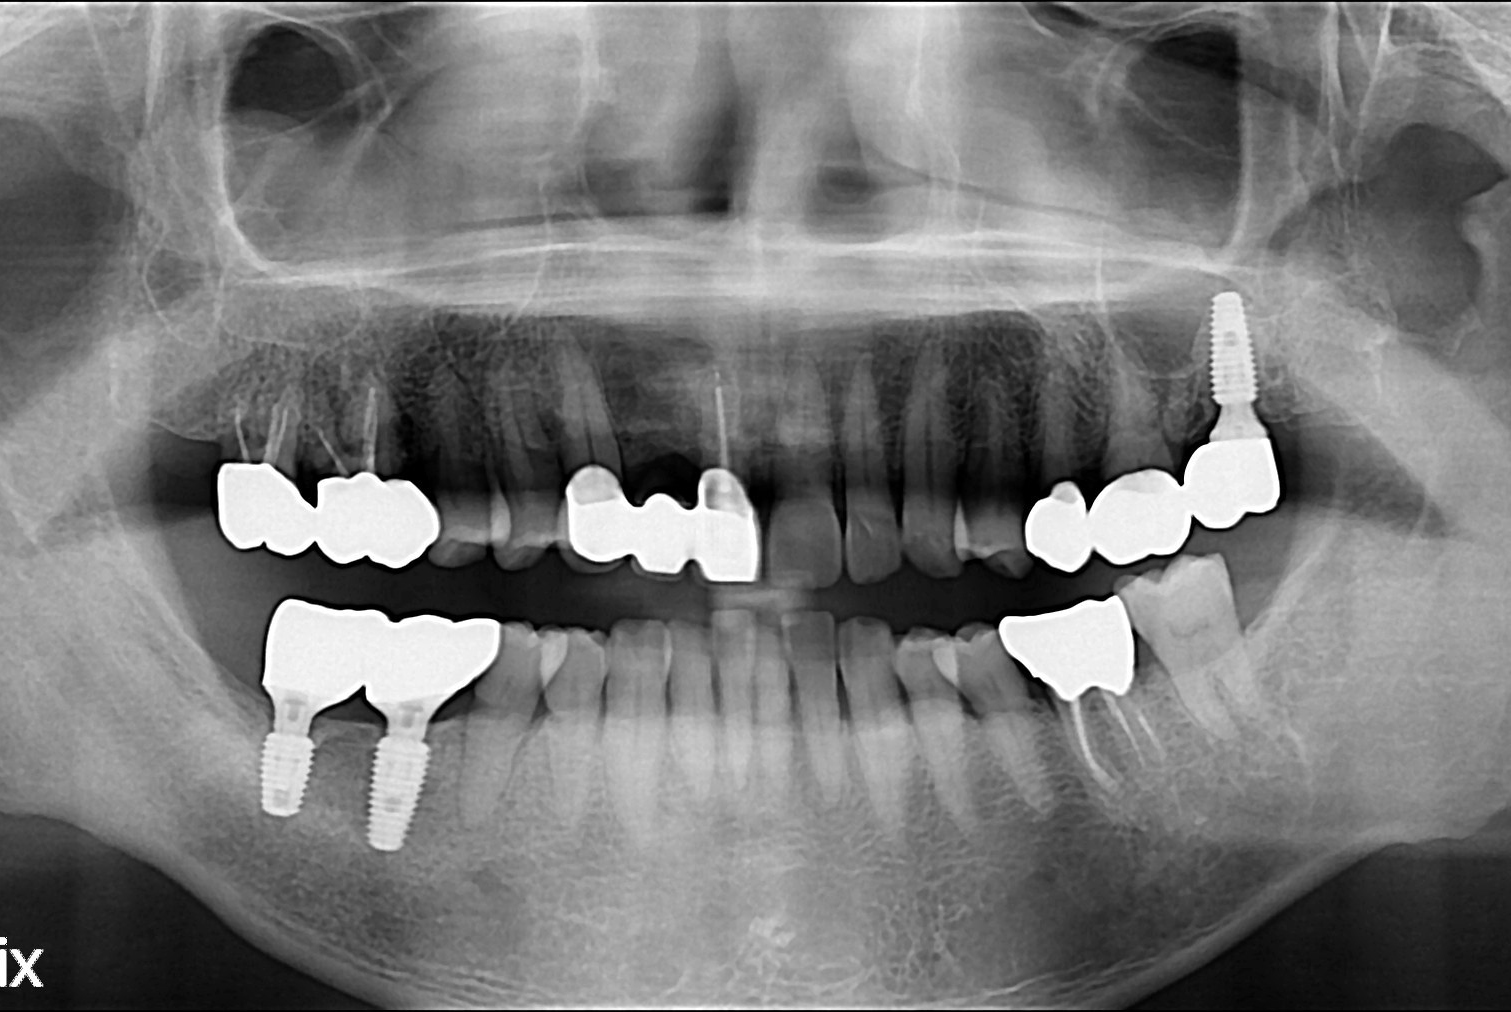

[임플란트] 임플란트

치료전 : 2018-03-14

임경민 후.jpg

치료후 : 2018-04-27

세종치과는 많은 환자와 다양한 케이스를 바탕으로 항상 편안한 임플란트 수술을 제공하고자 노력하고,

오래동안 튼튼히 쓸 수 있는 임플란트 수술을 가장 큰 목표로 삼고 있습니다